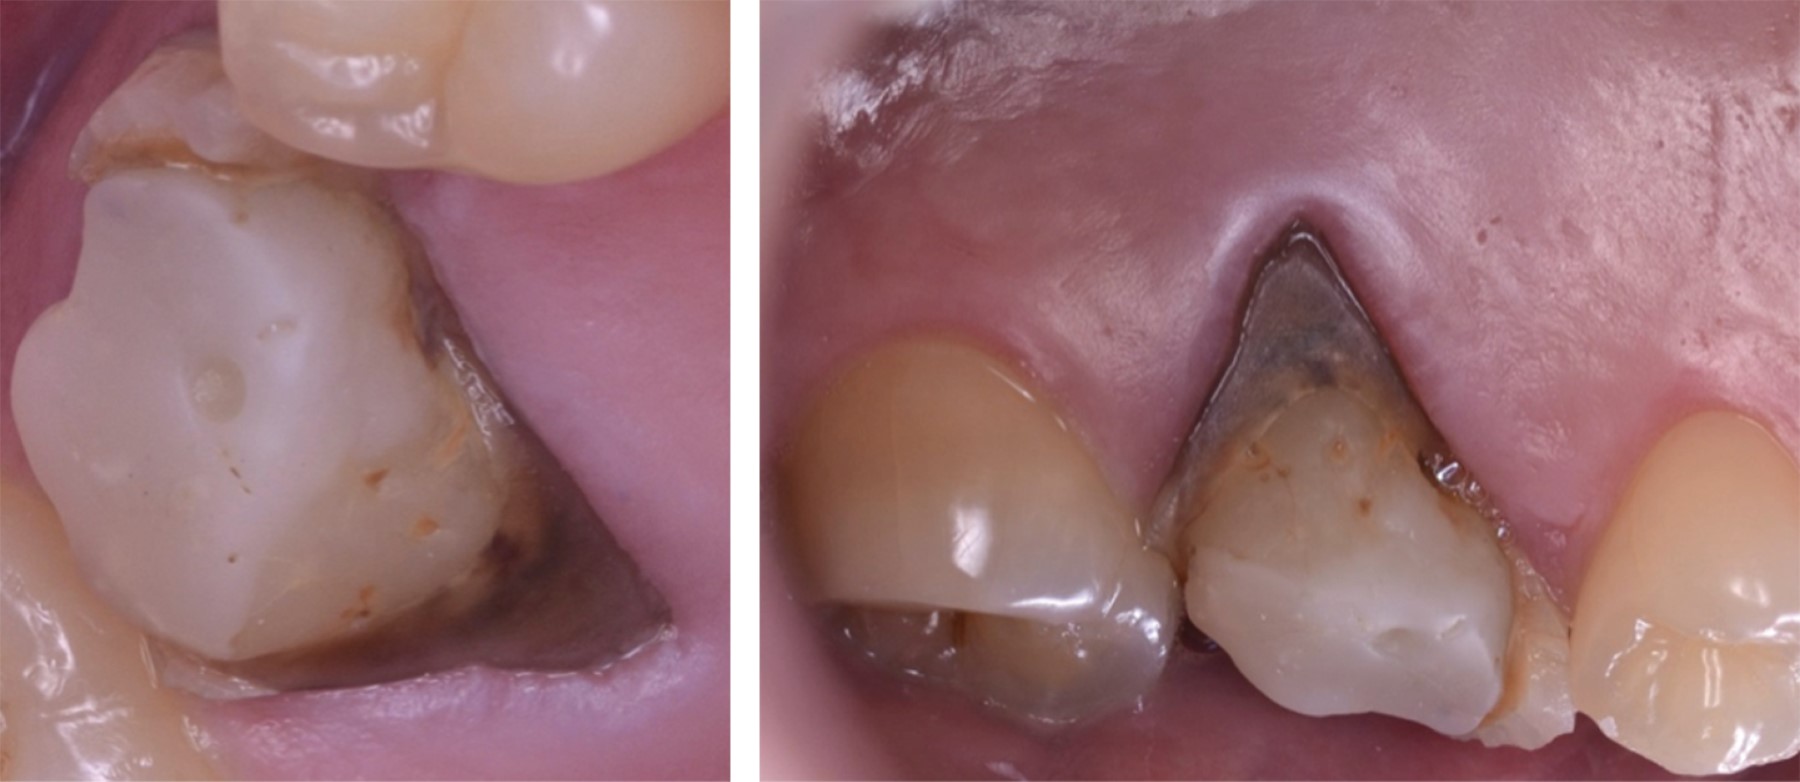

A la exploración clínica, se observó el primer molar superior derecho (OD #16) con aparente reconstrucción protésica, tejido dental remanente deficiente y una recesión palatina de en promedio cuatro milímetros y un sondaje en el sitio palatino de dos milímetros; lo que resulta en una pérdida de nivel de inserción clínica (CAL) de seis milímetros (Figura 1).

Figura 1